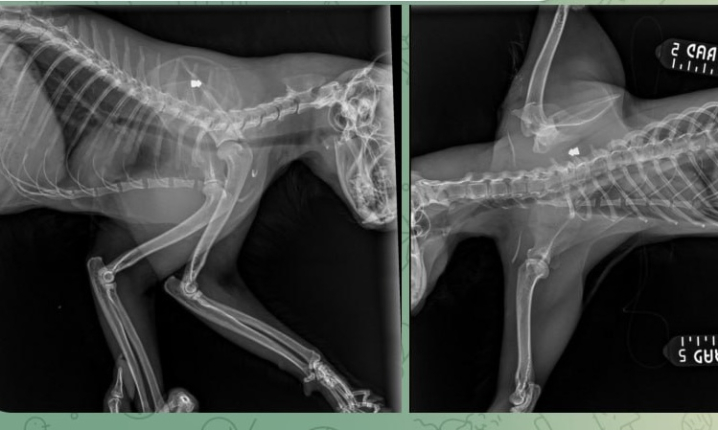

На рентгені видно кулю Реклама

На вулиці Сторожинецькій у Чернівцях невідомі стріляють у тварин.

«На початку вулиці Сторожинецької нелюди стріляють в тварин. Мого кота підстрелили», - йдеться у повідомленні.